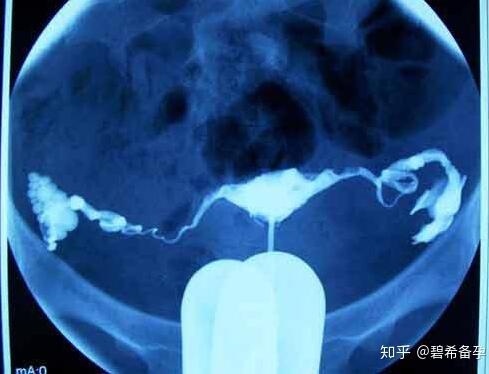

子宫输卵管造影(Hysterosalpingography,HSC),简单说就是,先用导管向子宫腔及输卵管注入造影剂,然后通过拍片,根据显影情况了解输卵管是否通畅。

此外,造影剂除了检查作用以外,还可以起到润滑、疏通输卵管的作用,对于输卵管的轻度粘连有一定治疗效果。

在简单消毒后,医生会往宫腔内插入导管并注入适量的造影剂,然后观察造影剂在输卵管及盆腔内的显影情况。